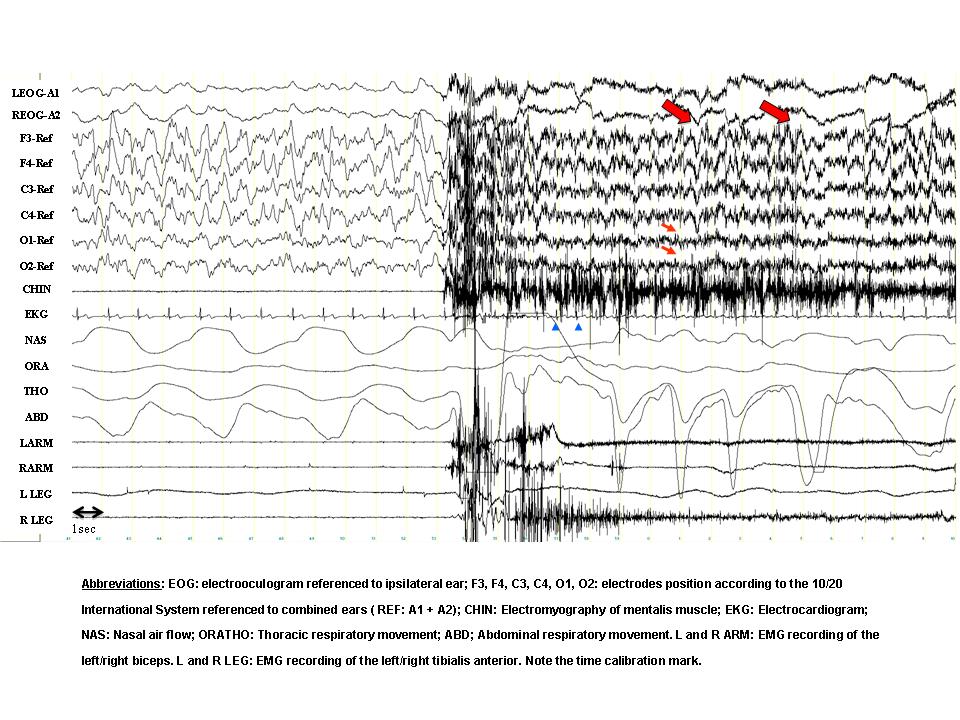

A 23-year-old female complained of abnormal behaviors during sleep that began at the age of 6 years. The episodes appeared within the first 1-2 hours of sleep and were relatively frequent (7-15 per month). She often recalled dreaming during the episodes. Typical dream contents were that she was locked in a hole without air or that she had been buried alive and she strongly needed to escape. Her bed partner referred that the episodes often began with the patient immediately leaving the bed, running and opening doors or windows with her eyes open, without awakening. The patient would have partial recall (“fragments”) or no recall at all of the episodes. A nocturnal polysomnographic (PSG) recording after 38 hours of sleep deprivation was performed and the panel shows a 30-second epoch containing one of the events.

- Stage N3.

- There is a sudden awakening directly from stage N3. In the occipital derivations (small arrows) the slow activity decreases in amplitude. In the frontal channels, however, there is persisting delta activity (large arrows), superimposed with EMG artefact. Note the sudden increase in heart rate (arrowheads in the EKG channel). In this particular episode the patient opened her eyes, sat up in bed with fear and spoke unintelligibly. She appeared disoriented and looked around in the room. In a few seconds, however, she relaxed and continued sleeping. The episode can be classified as a confusional arousal.

PSG recordings during the episodes often demonstrate (a) diffuse, rhythmic and synchronous delta activity, most prominent in bilateral anterior regions, or (b) diffuse and irregular moderate-to-high voltage delta and theta activity intermixed with, or superimposed by, alfa and beta activity. This high-amplitude slowing during the event is considered a hallmark of disorders of arousal, although it is non-specific. There is no epileptiform activity or sleep disorder breathing [1, 4].

The presence of wake-like EEG activity (alfa and beta activity) intermixed with high-amplitude slow activity could indicate a coexistence of NREM sleep and wakefulness [3] during the event. This is supported by the recording of an increase in regional blood flow in the posterior cingulate cortices with a simultaneous decrease in the frontoparietal associative cortices in a SPECT study during an episode of sleepwalking [5]. An intracerebral EEG recording during an episode of confusional arousal also found simultaneously fast EEG activity (similar to wakefulness) in motor and cingulate cortices (local arousal) and enhancement of delta activity in the frontoparietal associative cortices (local sleep) [2].